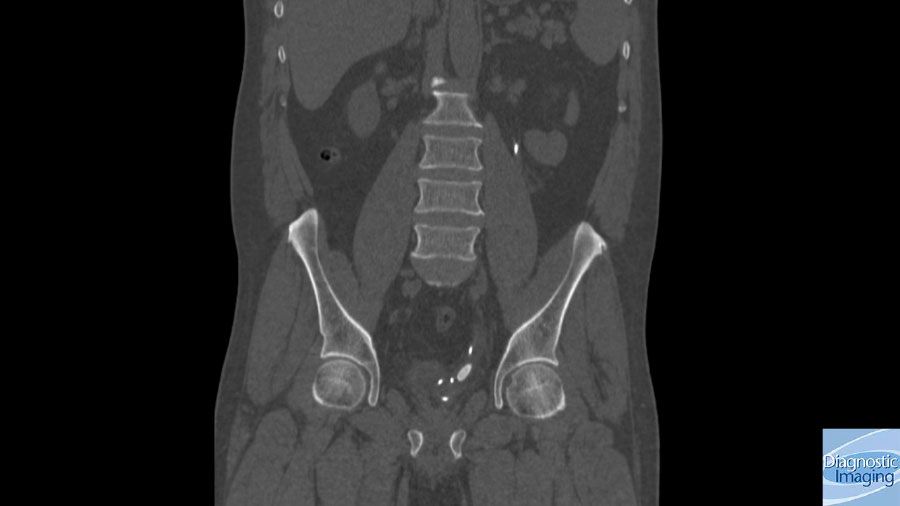

Case History: 50-year-old patient with ureteral stent evaluated with CT.